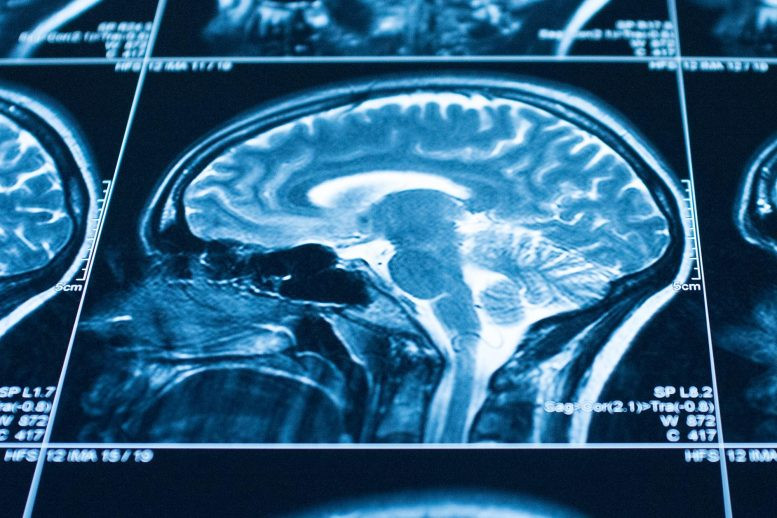

Hoạt động não liên quan đến sự đồng cảm khi quan sát một nạn nhân bị đau đã giảm khi tuân theo mệnh lệnh. Ảnh: Tiến sĩ Emilie Caspar.

Những người tham gia thử nghiệm được đặt máy quét MRI để ghi lại hoạt động não bộ của họ trong quá trình thực hiện nhiệm vụ. Những người đóng vai tác nhân được cho biết rằng họ có hai nút: một nút kích hoạt gây đau thực sự, đau nhẹ trên tay nạn nhân để đổi lấy 0,05 euro, và một kích hoạt khác không gây đau và không có tiền.

Các tác giả quan sát thấy rằng những người gây ra nhiều cú gây đau cho nạn nhân khi họ được hướng dẫn cưỡng chế hơn là khi họ tự do quyết định. Kết quả hình ảnh thần kinh cho thấy các vùng liên quan đến sự đồng cảm ít hoạt động hơn khi tuân theo mệnh lệnh so với hành động tự do.

“Chúng tôi cũng quan sát thấy rằng việc tuân theo mệnh lệnh làm giảm sự kích hoạt ở các vùng não liên quan đến cảm giác tội lỗi”, nghiên cứu sinh Kalliopi Ioumpa, đồng tác giả đầu tiên của nghiên cứu này giải thích.

Quan sát cho thấy việc tuân theo mệnh lệnh gây đau làm giảm sự kích hoạt ở các vùng não liên quan đến cảm thông và cảm giác tội lỗi đã giải thích ít nhất một phần lý do tại sao mọi người có thể thực hiện các hành vi vô đạo đức đối với người khác khi bị ép buộc.